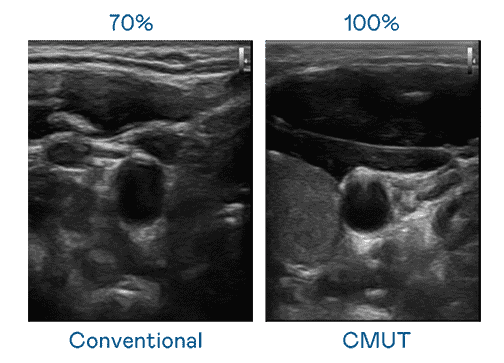

CMUT 技术是一种用电容式微机电元件来产生超音波讯号的技术。。与传统 PZT 压电式技术相比,,,CMUT 频宽增加 30%,,,,更宽频的超音波讯号让影像解析度大幅提升,,,,是实现高影像品质医疗超音波扫描、、促进精准医疗发展的关键技术。。

大频宽带来超清晰影像

超音波影像的解析度高低,,,,首先取决于探头能发出的讯号频宽。。。彩霸王 CMUT 可提供高清晰的超音波讯号,,,,提供高频宽、、、高灵敏度、、、影像纹理细节更高的超音波影像,,协助医护人员缩短影像判读时间及利用精准的医疗影像进行诊断。。。